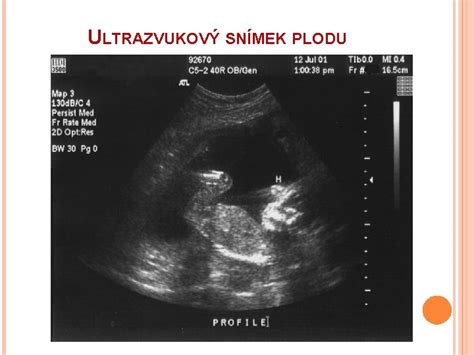

NT Scan je ultrazvukové vyšetrenie, ktoré sa zvyčajne vykonáva v období medzi 11. a 14. týždňom tehotenstva. Počas tohto skenovania sa meria hrúbka nazhromaždenej tekutiny v podkožnom priestore na zadnej strane krku plodu. Táto tekutina sa nazýva nuchálna translucencia (NT).

Príkladom normálnej hodnoty je hrúbka menšia ako 3,5 mm, ktorá sa vo všeobecnosti považuje za normálnu pre plod vo veku 11. až 14. týždňa tehotenstva. Výsledky tohto vyšetrenia sa zvyčajne uvádzajú ako pomer rizika, napríklad 1:100, čo znamená, že jedno z 100 tehotenstiev má vyššie riziko danej abnormality.